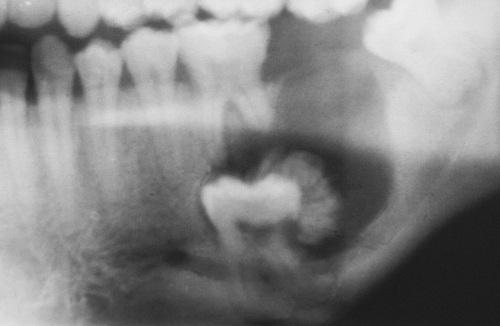

Radiolucent defect in the ramus containing small calcifications having the radiodensity of tooth structure.

ameloblastic fibro-odontoma

Unilocular radiolucent defect displacing the developing mandibular third molar posteriorly. Flecks of mineralized material are present in the radiolucent defect.